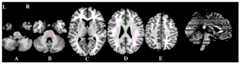

An example of the variable selection of a depression patient by the above method is shown in fig. 2, and fig. 2 is an interaction analysis graph of diagnosis x time point in step 4Aa, in which (a) is the left temporomandibular gyrus, (B) is the right cerebellar gyrus, (C) is the left lingual gyrus, and (D) is the left dorsal medial prefrontal gyrus. L represents the left hemisphere, and R represents the right hemisphere.

Further regression analysis found that DC changes in the D brain region shown in fig. 2, i.e., the left dorsal medial prefrontal gyrus, correlated with the extent of clinical remission in depression patients (B3.404, p < 0.001).